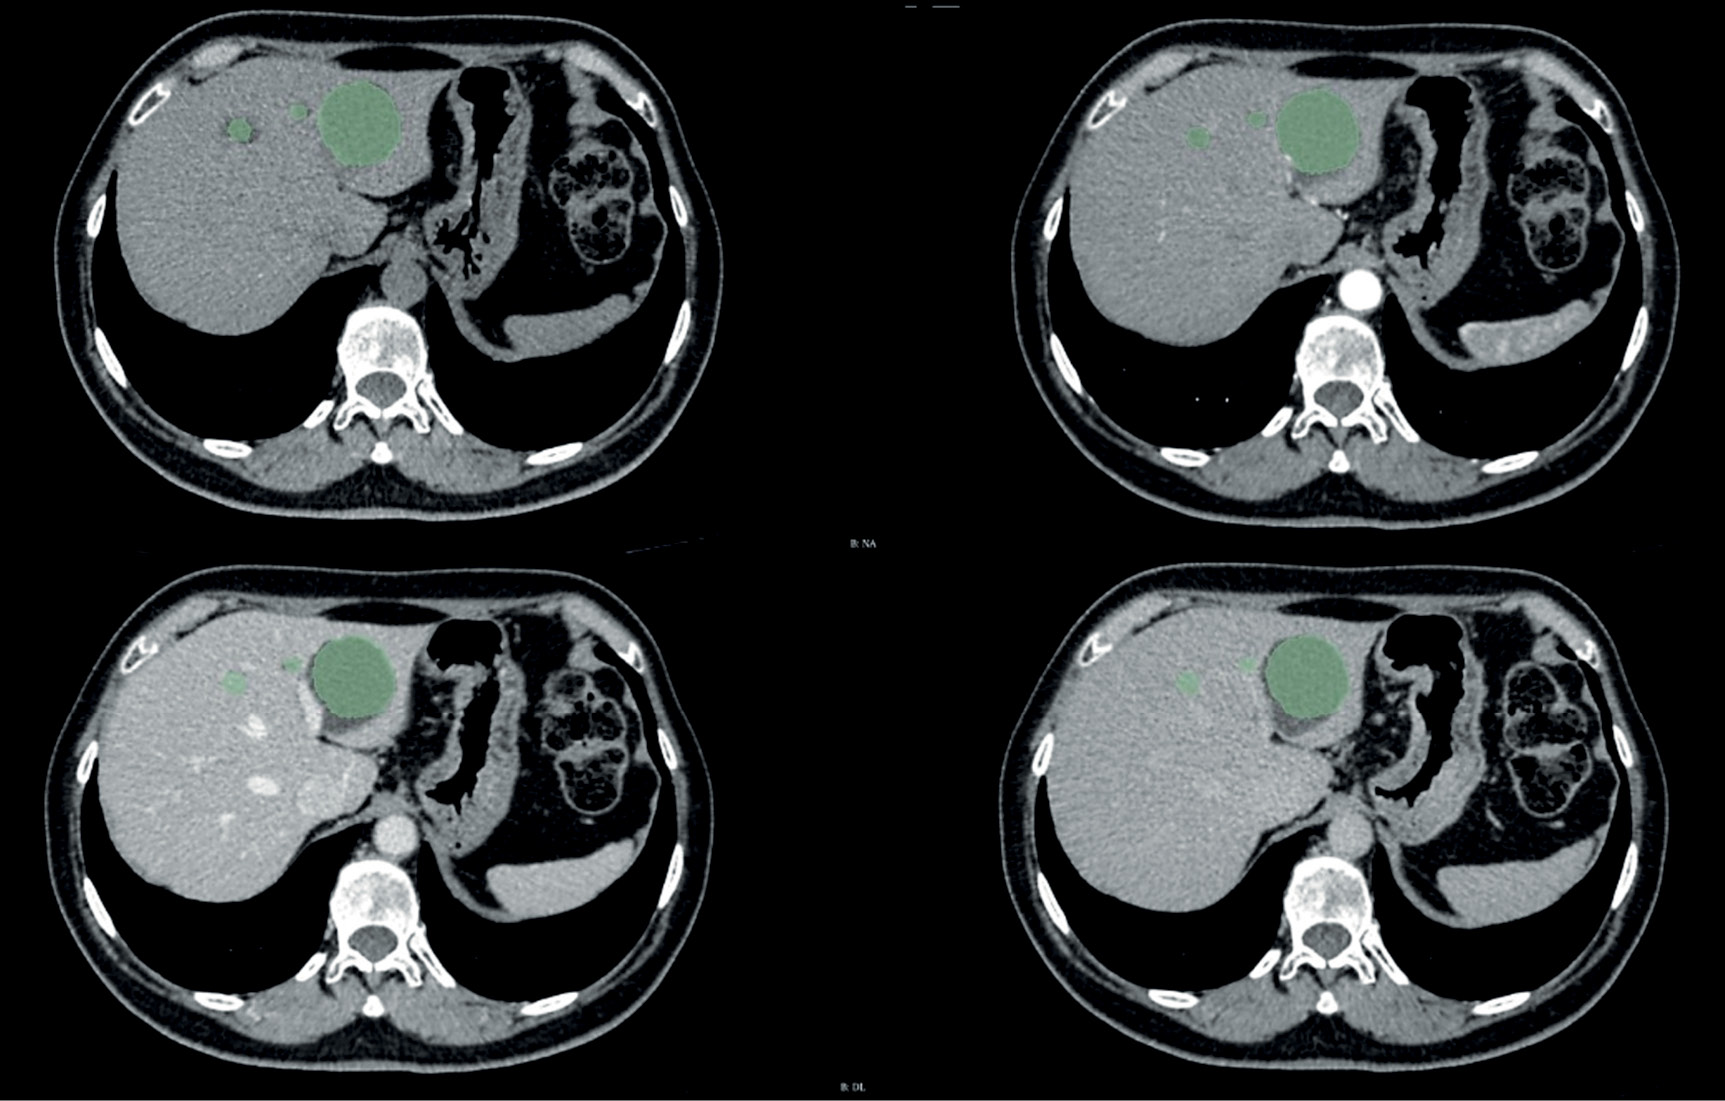

The Center for Diagnostics and Telemedicine (Moscow) is currently developing a computer vision algorithm using contrast enhancement for within-class segmentation and differentiation of liver masses. An example is presented in Fig. 2.

Fig. 2. An example of liver neoplasm segmentation by an algorithm based on a contrast-enhanced CT scan.